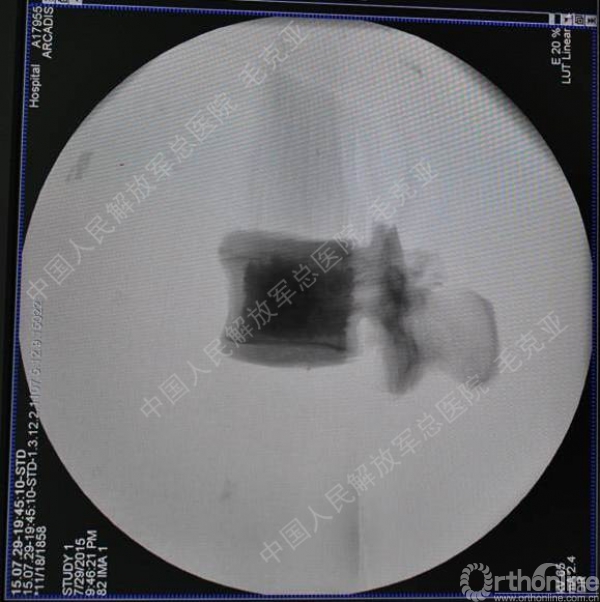

导语:随着社会老龄化的不断加速,骨质疏松性椎体压缩骨折作为一种普遍存在的老年骨科疾病已经成为现今骨科界的一个热点话题。传统的保守疗法治疗效果不佳,而现有的椎体增强技术又具有多种风险和缺陷。针对这种现状,中国人民解放军总医院毛克亚教授提供了一种新的解决方法。